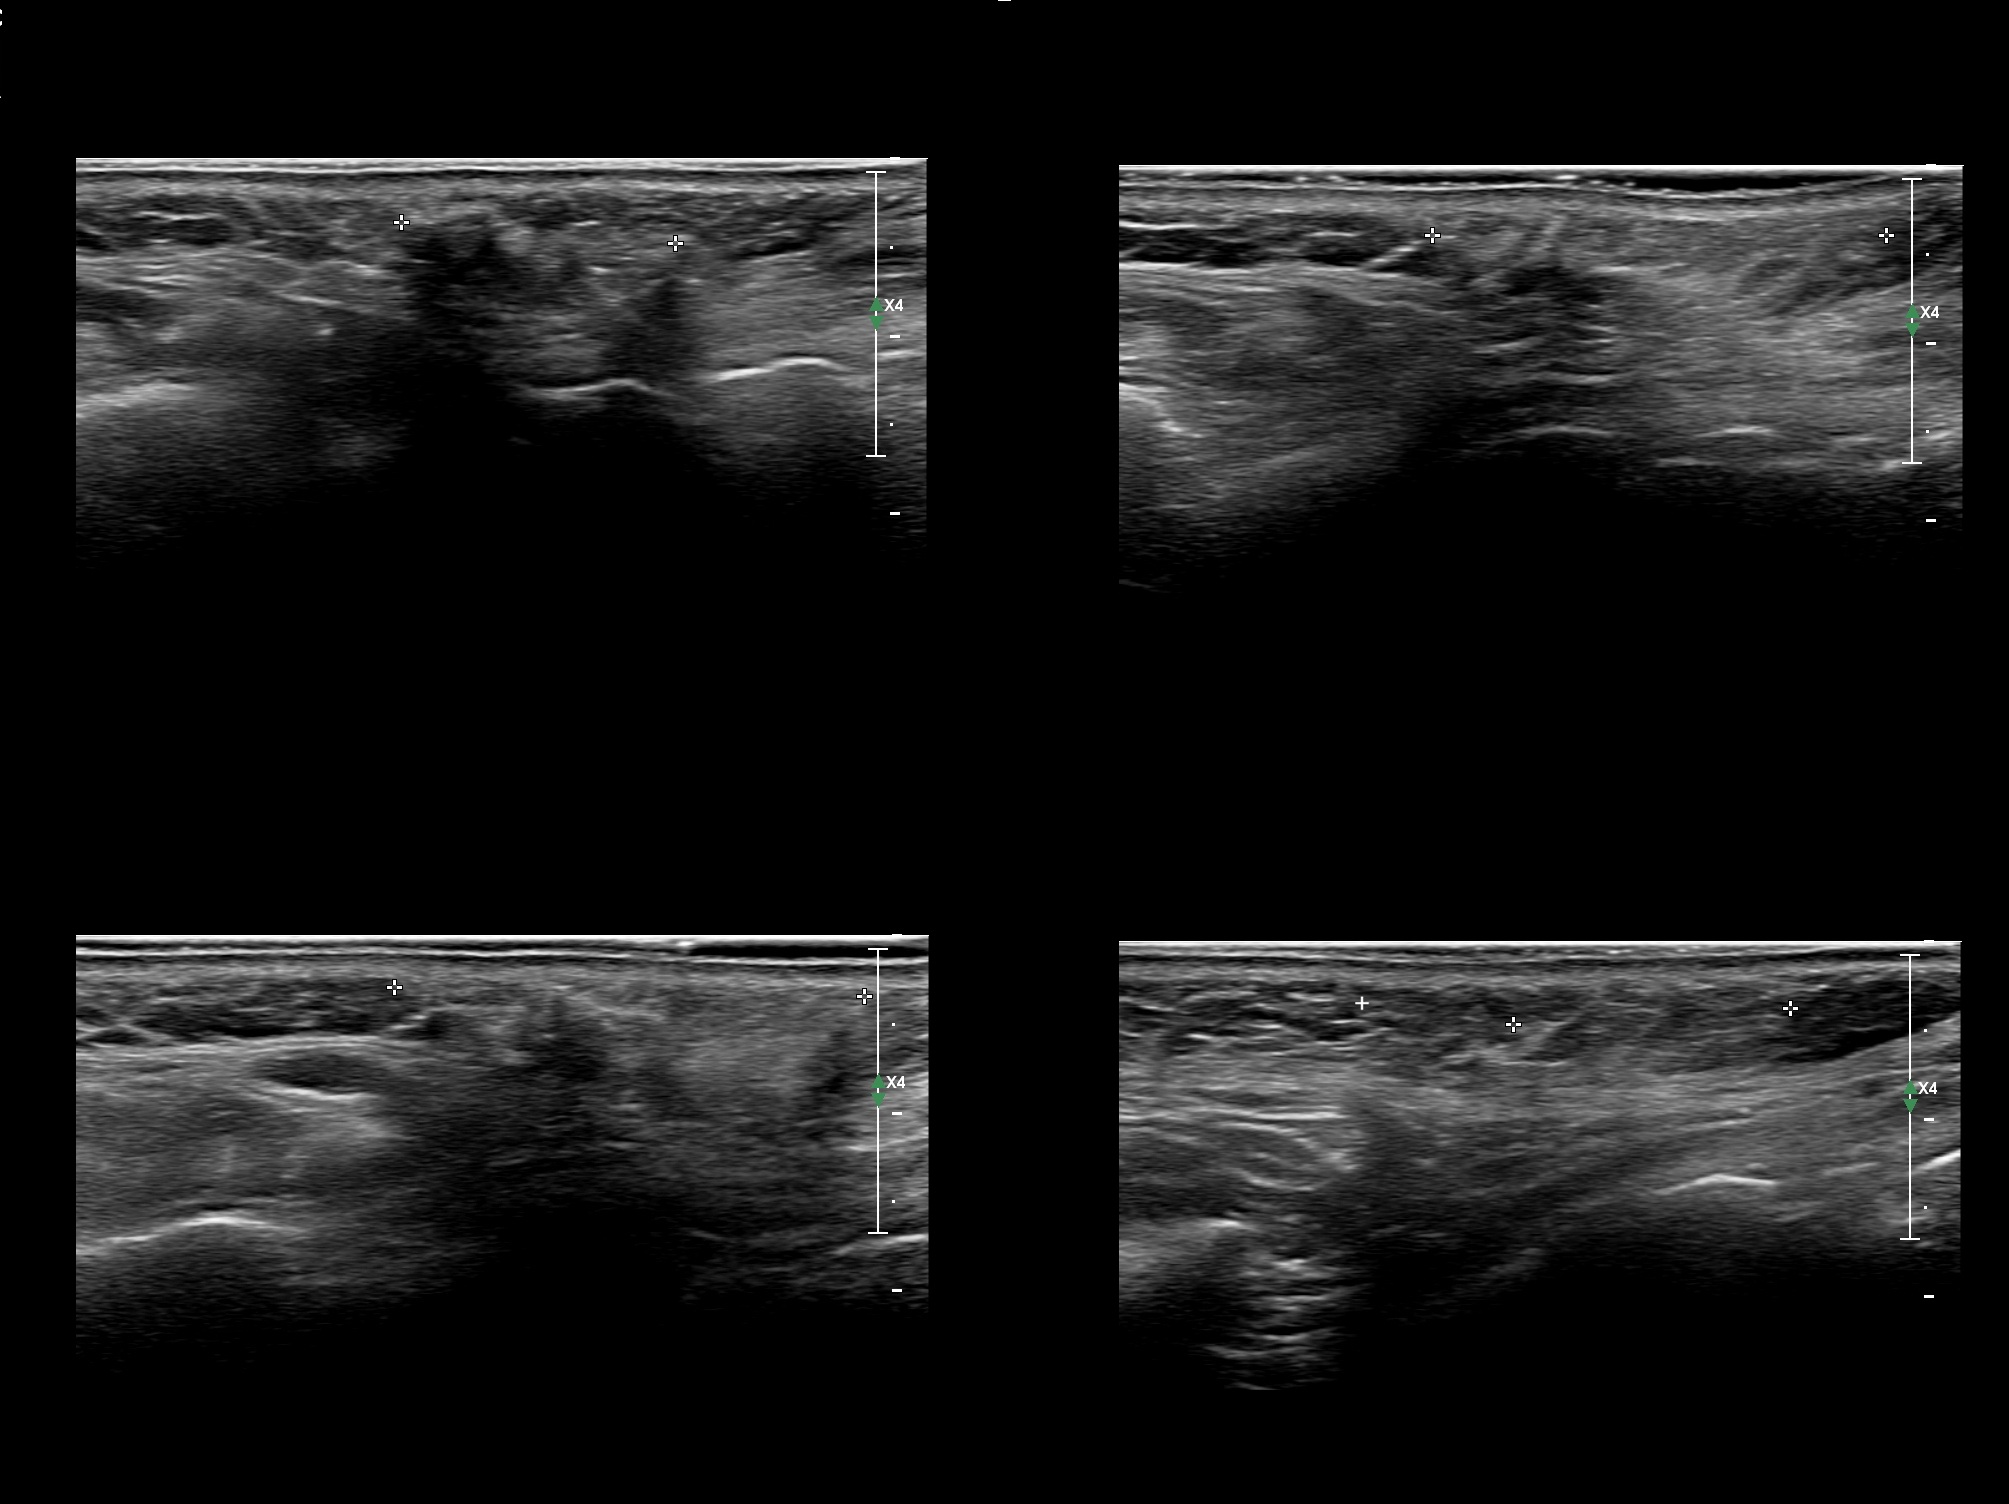

Fillers

Draw in the second image below where the fillers are located. To check if your answer is correct, swipe the first image to the right.